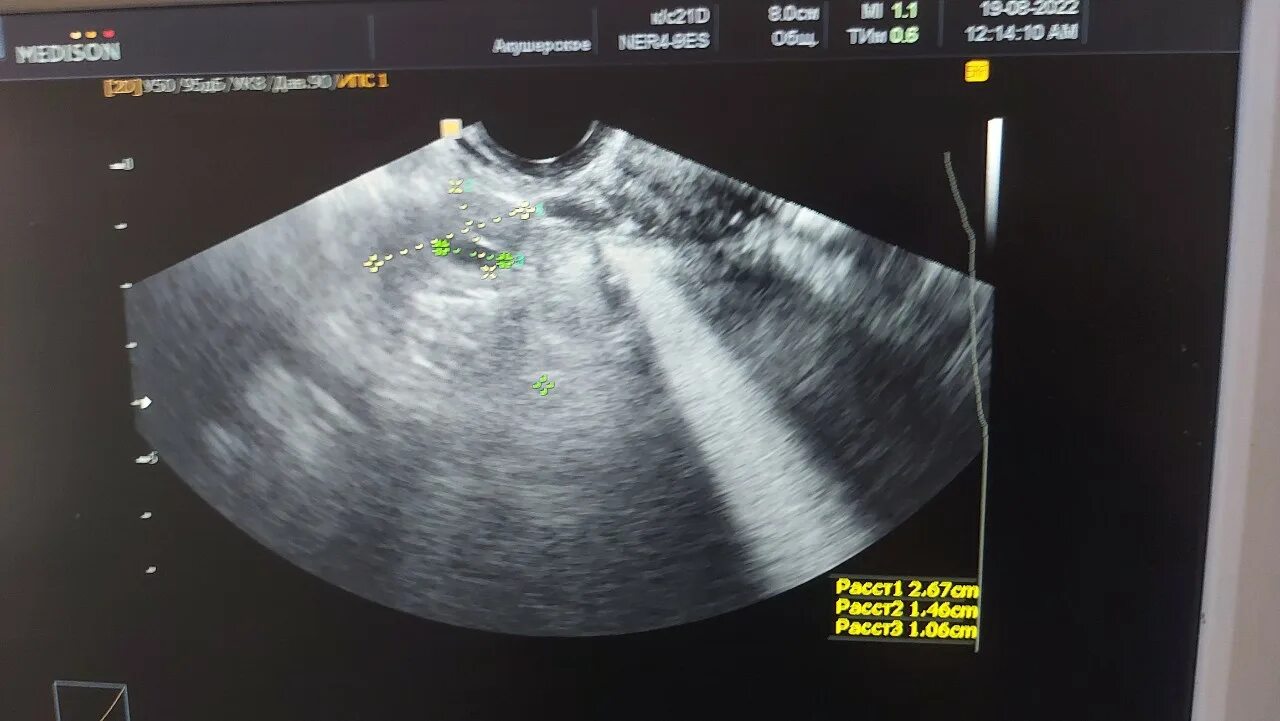

Поищите анемо метки в трех разных